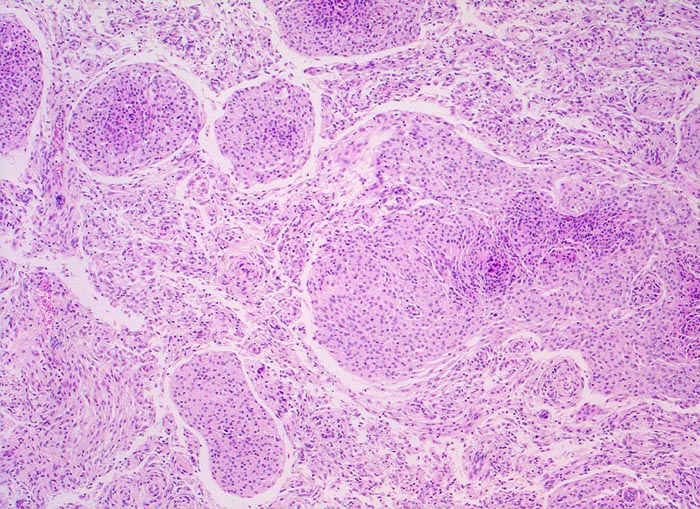

PathoPic – image database / PathoPic ID 5194 - meningotheliales Meningeom (WHO I)

meningotheliales Meningeom (WHO I)

Klassisches Meningeom bestehend aus teils kugeligen Verbänden monomorpher Tumorzellen. Zwischen den Tumorzellverbänden kleine Gefässe und schmale Bindegewebssepten.

Wegen erstmalig aufgetretenem epileptischem Anfall wird ein Schädel CT durchgeführt. Dabei kommt über der rechten Grosshirnkonvexität ein 3cm grosser runder Tumor zur Darstellung. Der Patient litt ausserdem seit mehreren Wochen über rechtsseitig lokalisierte Kopfschmerzen.